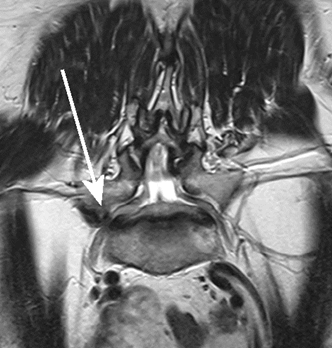

(특수 MRI 촬영상 좌측에 비해 우측의 신경이 지나가는 부위가 좁아진 것이 명확하게 보인다)